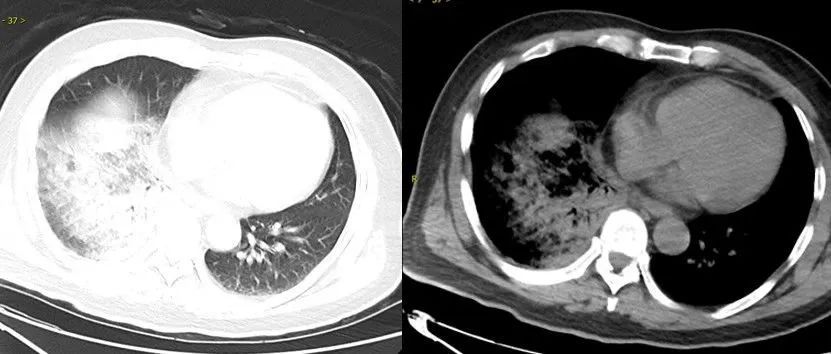

鹦鹉热衣原体肺炎影像示例。图源:江苏省人民医院

相比于一般细菌引起的肺炎,“鹦鹉热”常伴有各种各样的肺外表现,如神经系统症状(头痛、精神状态改变)、消化道症状(呕吐、腹痛,肝功能异常)。

部分病例可致重症肺炎,甚至出现呼吸衰竭、心肌炎、脑炎等严重并发症,危及生命。